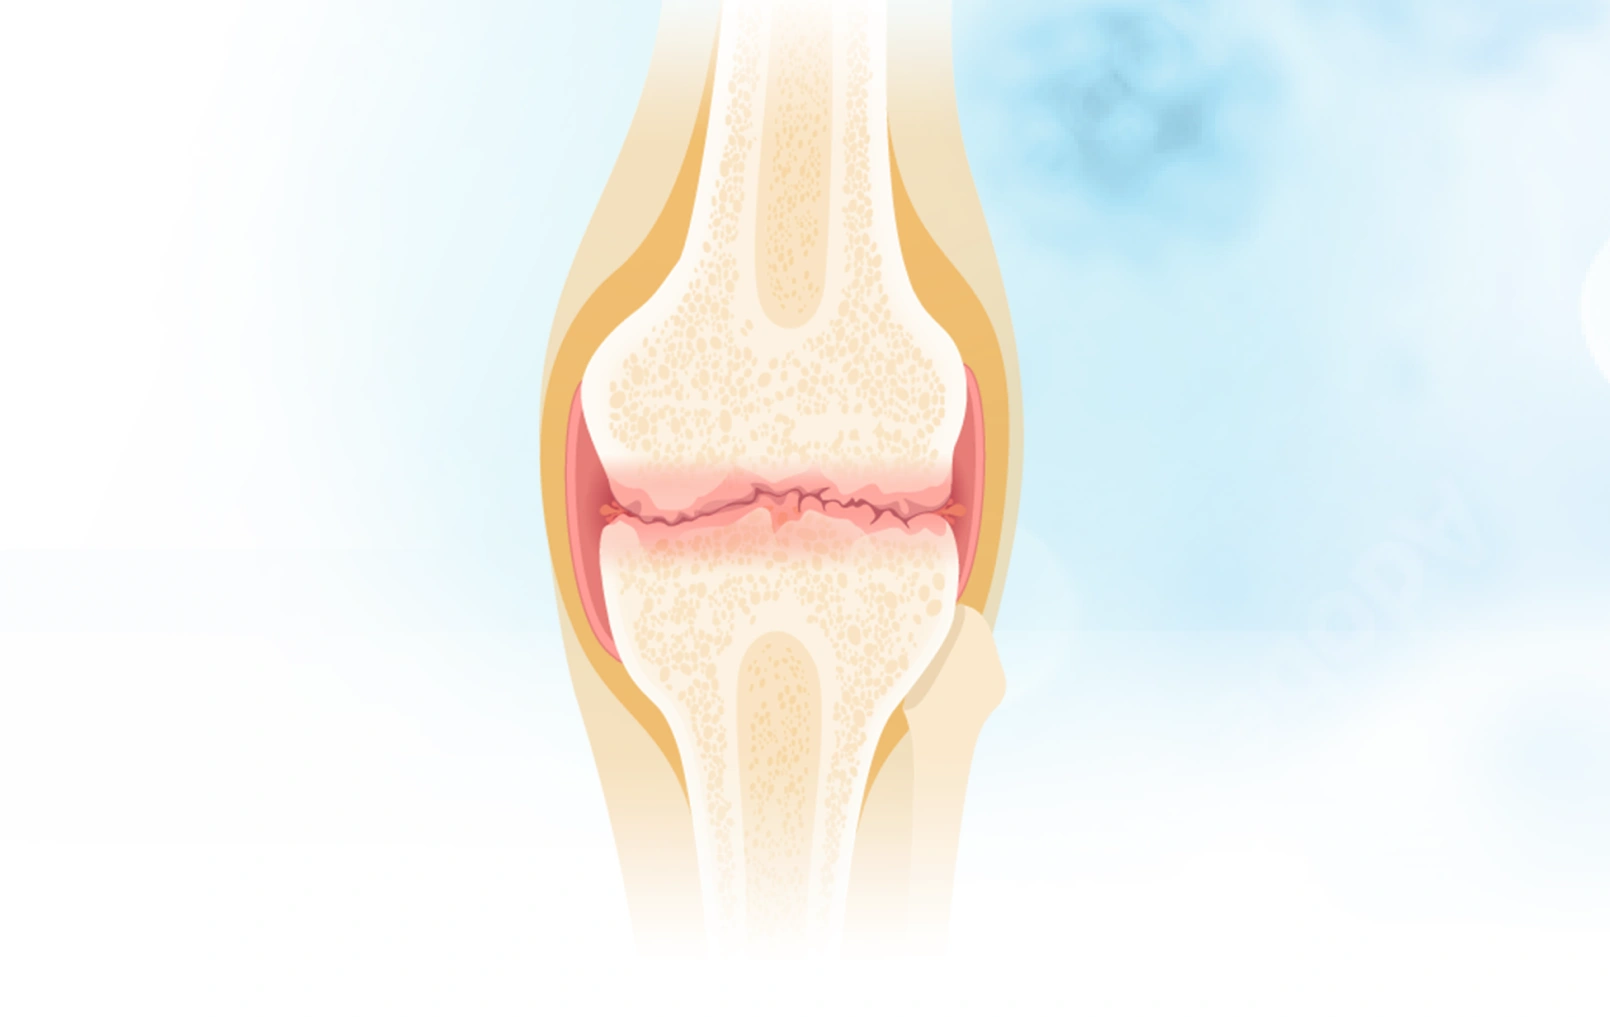

关节里的“减震器”去哪了?深度拆解骨关节炎的本质

骨关节炎不是一个突然降临的诅咒,而是长期“错误使用”身体的结果。 请记住: 软骨(减震垫)需要被温柔对待。 滑液(机油)需要通过科学运动来保持新鲜。 全...

骨关节炎的病理生理机制

你有没有想过,为什么有些人50岁就膝盖疼得上不了楼,而有些人80岁还能爬山? 为什么关节里那层看似不起眼的软骨一旦出问题,就能让一个人从"健步如飞"变成"举步...